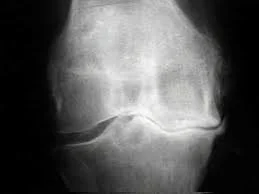

OSTEOARTHRITIS

It is characterized primarily by a loss of cartilage around a joint, which helps to provide smooth gliding of a joint, and results in pain and swelling and loss of range of movement in a joint.